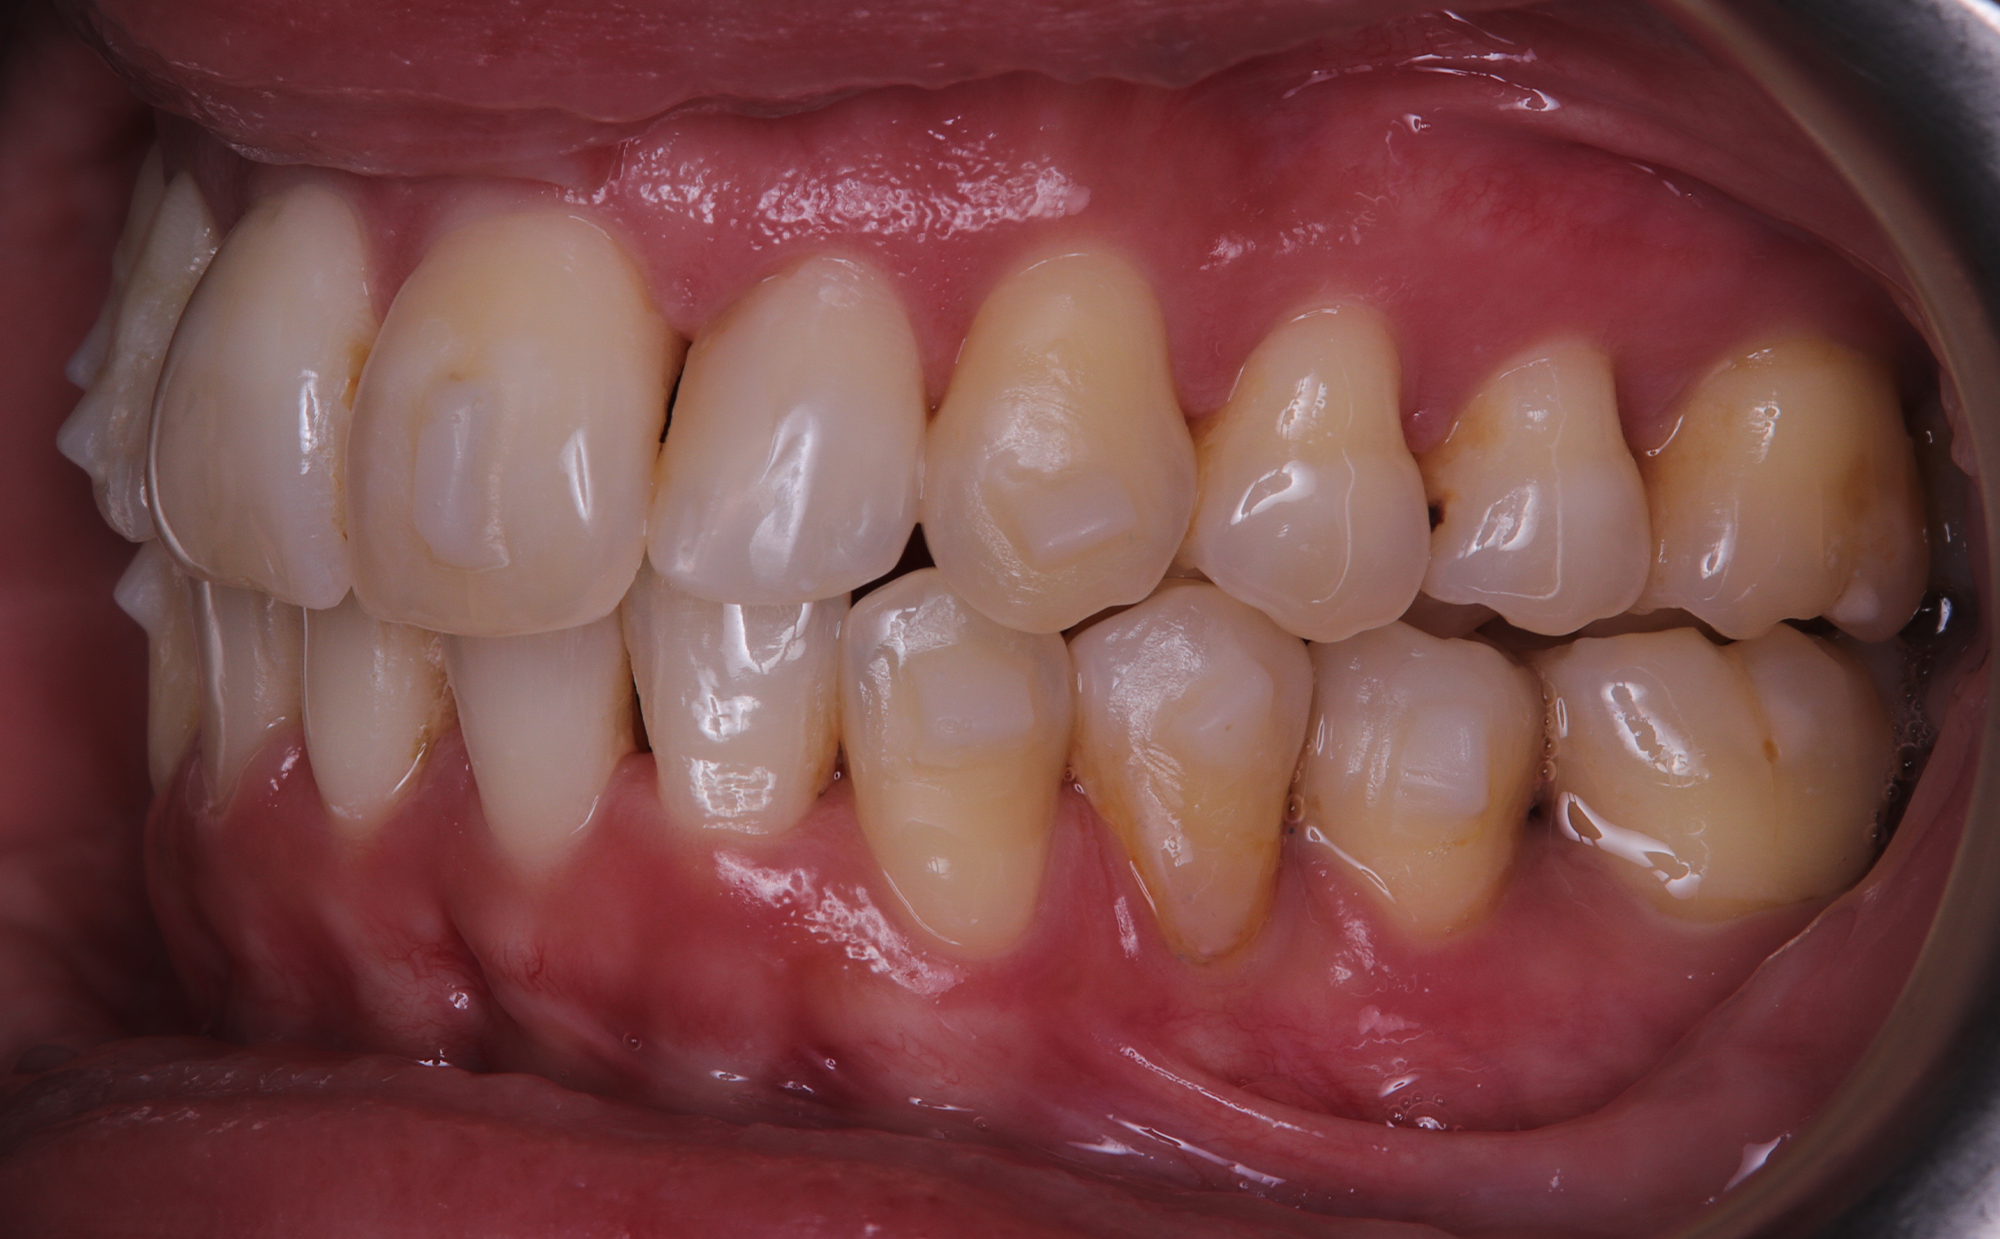

The patient, having completed a periodontal treatment phase, presented with significant aesthetic and functional concerns due to moderate crowding in both arches and a pronounced anterior crossbite. Clinical examination confirmed the need for comprehensive realignment, particularly in the anterior region. Although the patient had a history of periodontal issues, radiographic evaluation showed no signs of active disease. Based on these findings, the treatment plan was designed to carefully modulate orthodontic forces to protect the occlusion and surrounding tissues while addressing the misalignment.

To correct the misalignment and anterior crossbite without compromising tissue stability, a slower orthodontic treatment plan was devised using the Spark Advanced clear aligner system. The initial phase involved 36 aligners designed to gently expand and realign the dental arches, limiting the rate of tooth movement. Strategic interproximal reduction (IPR) was performed in the anterosuperior region (between teeth #21 and #11) to create the necessary space for proper alignment while avoiding excessive loading on the tissues.